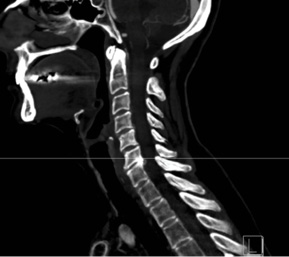

This patient is a 58 year-old female radiology technician with chronic, intractable neck pain, right > left arm radicular pain, and progressive weakness. At one point her symptoms worsened so acutely, she presented to the emergency department for acute triage with cervical CT angiogram, which showed advanced spondylosis at the C6/7 level.

The combination of the chronic problem with acute worsening of symptoms required decompression and stabilization at C6/7. Typically, at this patient age, with this advanced level of spondylosis at the C6/7 level, I would proceed with an instrumented fusion. However, this patient was very active and wanted to optimize her quality of life as possible with this surgery.

Patient is a healthy, active 58 year-old female, though with advanced degenerative spondylosis at a low cervical level. The patient had favorable anatomy with a long neck and low shoulders to facilitate intraoperative visualization. Fusion was appropriate in this case, but intraoperatively, though we were prepared for this possiblity, the disk space was well-preserved and mobilized without major modification of the endplates. The postoperative flexion and extension radiographs showed movement at the spinous processes of C6/7 and good function of the prodisc C Vivo prosthesis. The adjacent C5/6 level also shows degenerative spondylosis. By optimizing the mobility of the C6/7 level I anticipate the patient will have an improved trajectory for her cervical spine function throughout her life.